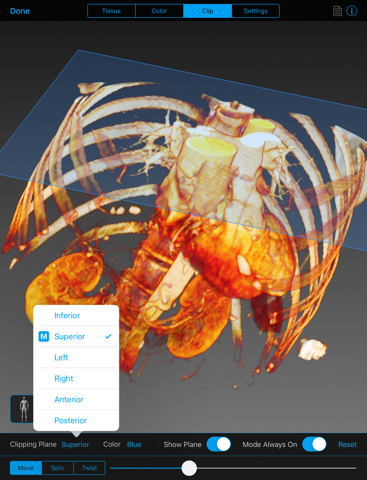

The BodyViz iPad app is a key component of the world’s most scalable 3D MRI/CT visualization suite for anatomy education and medical simulation. The BodyViz iPad app allows users to interactively rotate, pan and zoom through a patients virtual anatomy in 3D, using the familiar and intuitive iOS gesture interface. Clipping planes can be created and moved for virtual dissection to expose internal structures of the patient. Users can choose the tissue density they wish to view, such as harder tissues (e.g., bone, muscle) or softer tissue, like fat or skin. They can also choose from a variety of colors to enhance organs and other features of the data. Finally, the BodyViz iPad app enables users to view spatially registered annotations created with the BodyViz desktop application that can allow labeling of anatomical data as well as providing descriptions, web links, and images.

- Clipping of dataset in 3D from six orthogonal or user defined planes